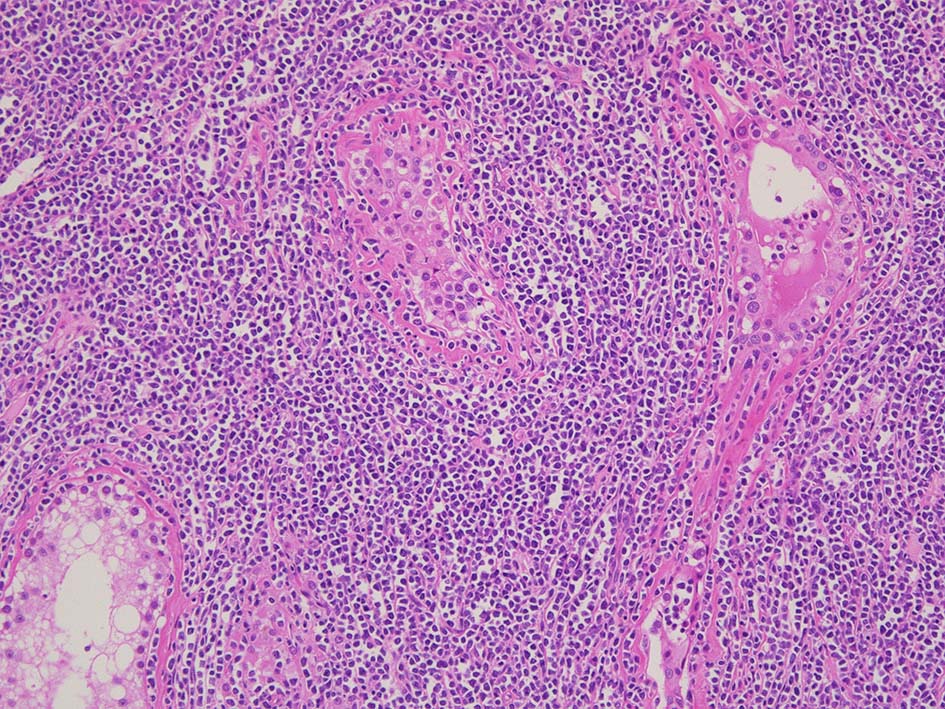

精細管は浸潤により萎縮, 消失. びまん性にcentroblasts/immunoblastsの増殖が認められる. 腫瘍細胞間に軽度の線維化がある.

増殖巣では精細管は消失, 萎縮. 腫瘍境界部での浸潤所見がある.